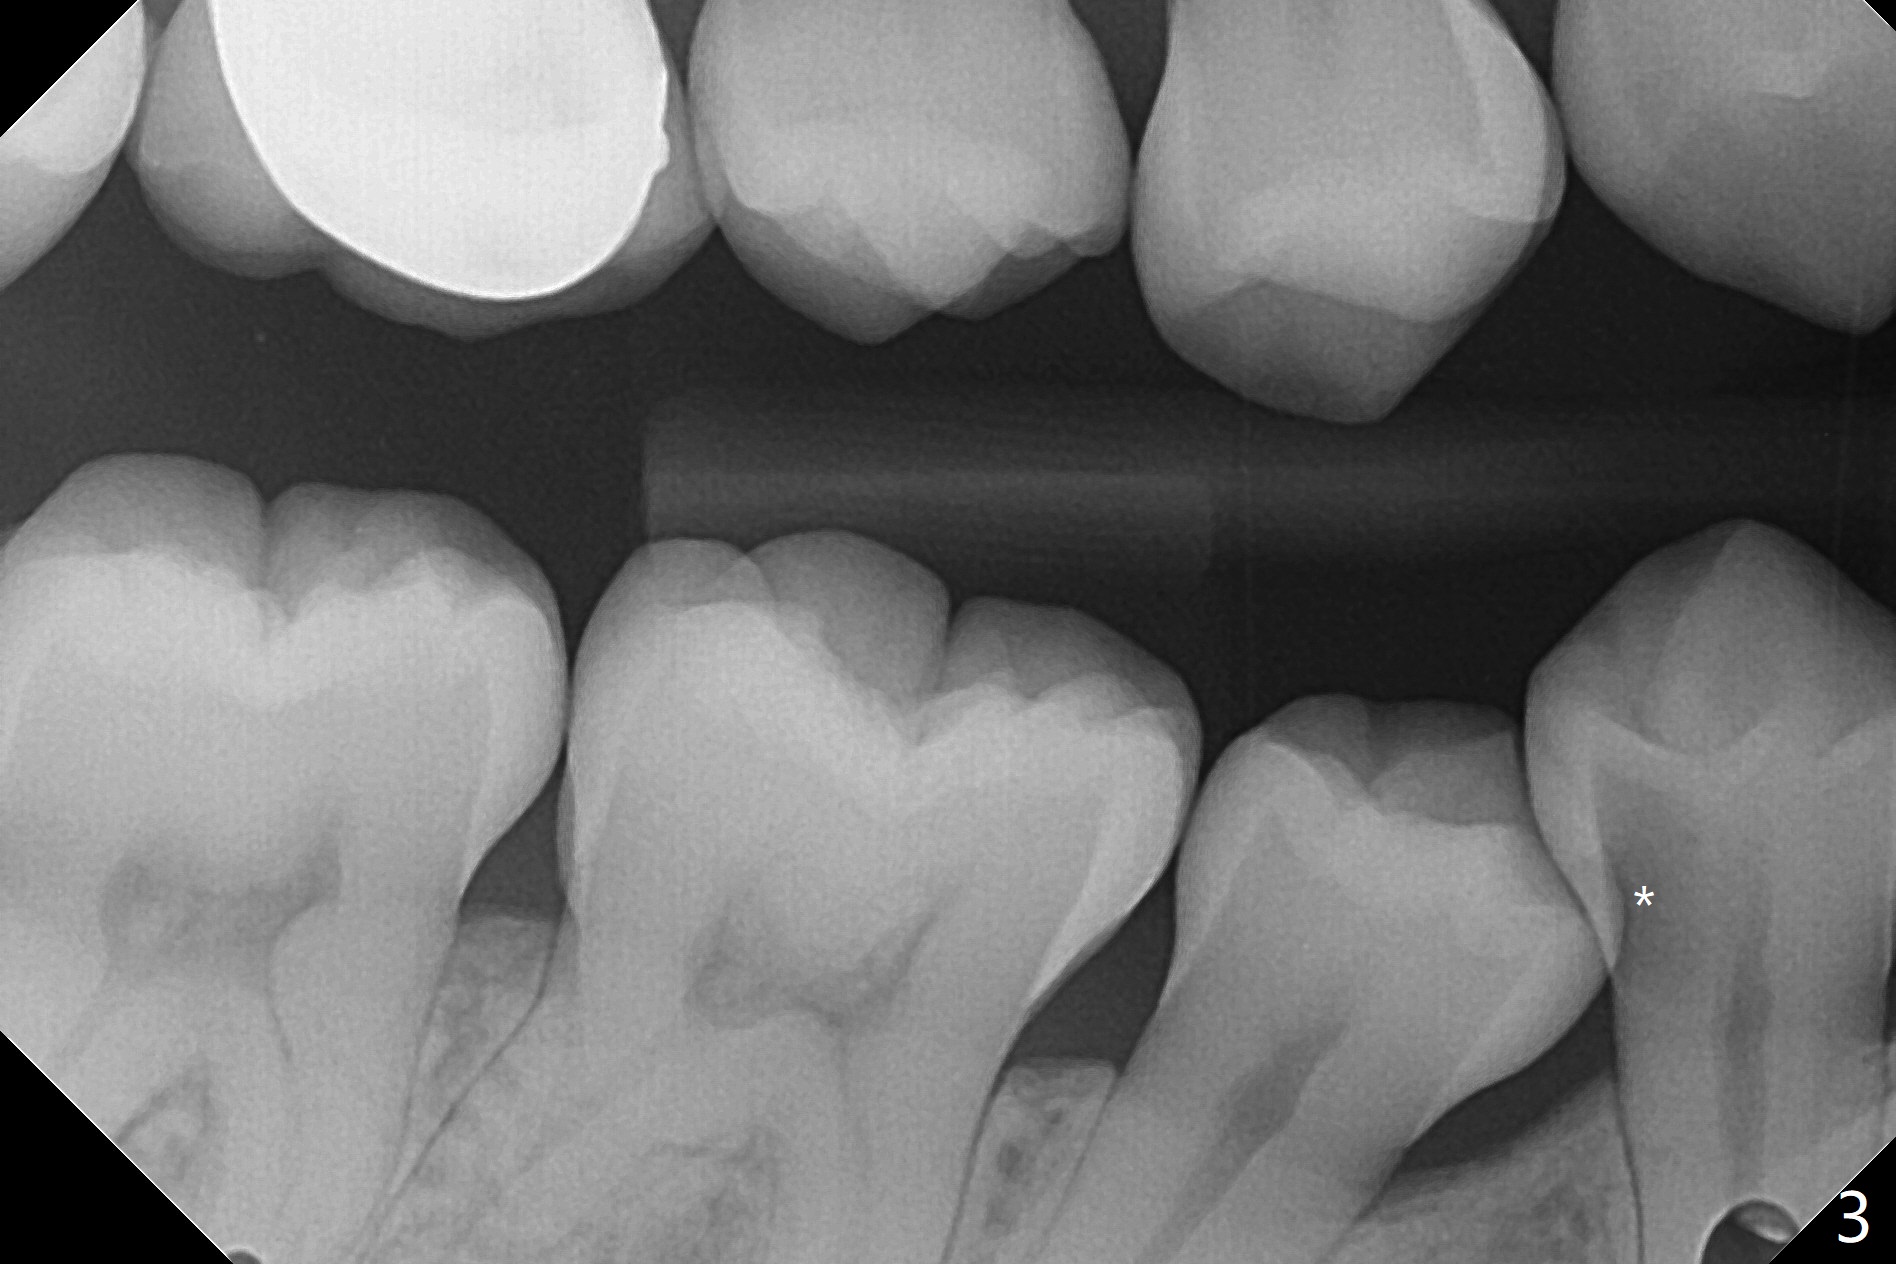

A 34-year-old woman with crowding particularly at LR 4/5 (Fig.1) and suspected DO caries of LR4 (Fig.2) returns with symptom of pulpitis and "cavity" at LR5 (MO). New Bitewing confirms LR4 DO caries (Fig.3). Treatment plan is to extract LR4 and place composite at LR5 if present. Extraction turns out to be difficult because of nervousness and TMD of the patient and crowding. The proximal areas of LR4 requires removal before luxation without traumatizing the neighboring teeth (Fig.4 insert black areas). In fact there is no caries at LR5. When the patient returns for orthodontic treatment, bracketing at LR5 should consider overcorrection (Fig.5 (black rectangle vs. red line: height of contour)) due to the tilted long axis (Fig.1).